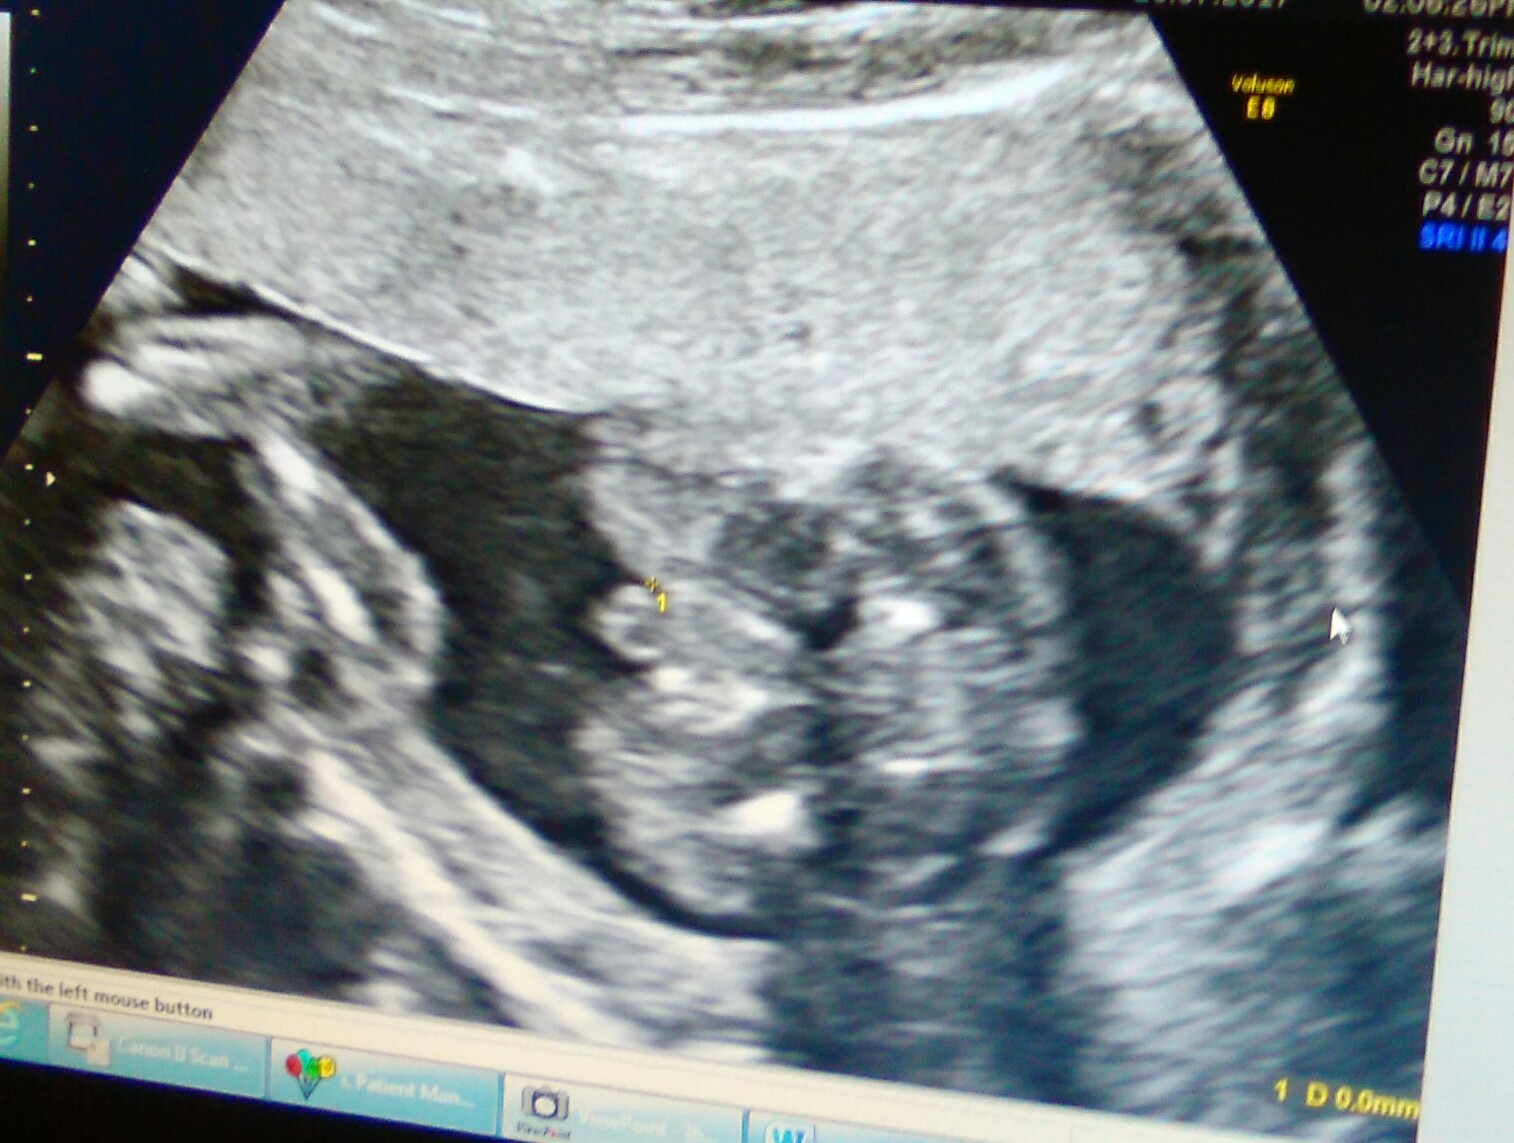

this is whats making me confused ...been told the turtle on top is the boy bit but look at this ..

i would think boy from these pics x

I think boy too